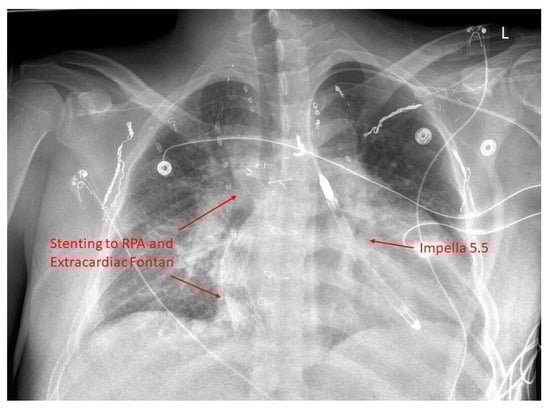

18. Advanced Therapies for Heart Failure

19. Mechanical Circulatory Support

- Coffman, Z.J.; Bandisode, V.M.; Kavarana, M.N.; Buckley, J.R. Utilization of an Abiomed Impella Device as a rescue therapy for acute ventricular failure in a Fontan patient. World J. Pediatr. Congenit. Heart Surg. 2019, 10, 518–519. [Google Scholar] [CrossRef]

- Morray, B.H.; Dimas, V.V.; Lim, S.; Balzer, D.T.; Parekh, D.R.; Van Mieghem, N.M.; Ewert, P.; Kim, D.W.; Justino, H.; McElhinney, D.B.; et al. Circulatory support using the impella device in fontan patients with systemic ventricular dysfunction: A multicenter experience. Catheter. Cardiovasc. Interv. 2017, 90, 118–123. [Google Scholar] [CrossRef]

- Tan, W.; Reardon, L.; Lin, J.; Lluri, G.; Venkatesh, P.; Bravo-Jaimes, K.; Biniwale, R.; Van Arsdell, G.; Ponder, R.D.; Aboulhosn, J. Occlusion of aortopulmonary and venovenous collaterals prior to heart or combined heart-liver transplantation in Fontan patients: A single-center experience. Int. J. Cardiol. Congenit. Heart Dis. 2021, 6, 100260. [Google Scholar] [CrossRef]